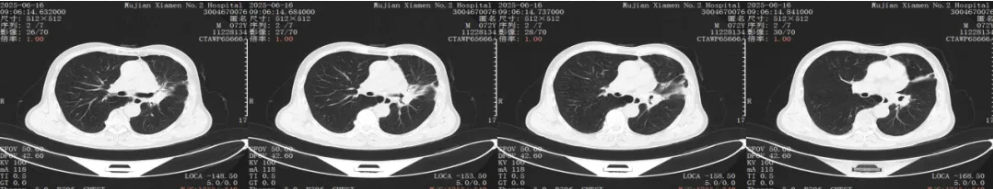

胸部CT平扫+增强:2025年2月20日末次用药,停用4月后复查

疗效评价:SD(近期于2025年6月16日复查CT,复查结果显示病情稳定)